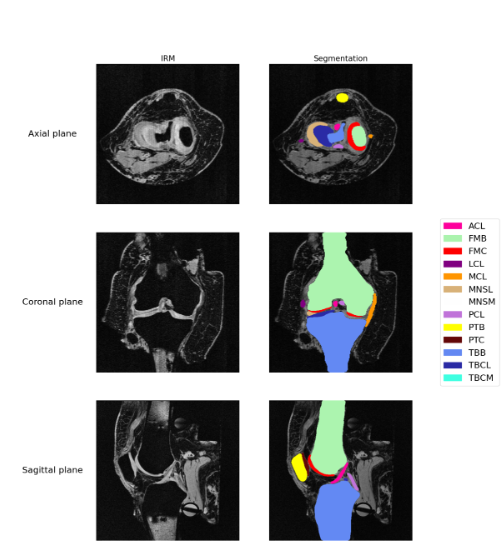

Knee MRI Segmentation Across Sagittal, Axial, and Coronal Planes

This project involves applying deep learning techniques to segment knee MRIs across all sagittal, axial, and coronal slices, enabling more accurate and comprehensive analysis.